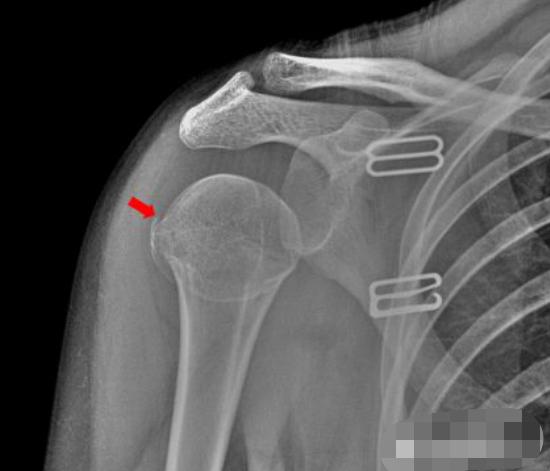

肩关节

1、患者摔倒,右肩关节着地,拍片如下:

右侧肱骨大结节骨皮质欠光整,见弧形透亮线。右侧肱骨大结节骨折。